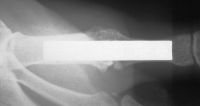

| The Synthes mini fragment

system was used, with a lag screw across the fusion site and

sesamoid excision. |

| Although the patient healed

uneventfully, the screws seem excessively large for these bones. |